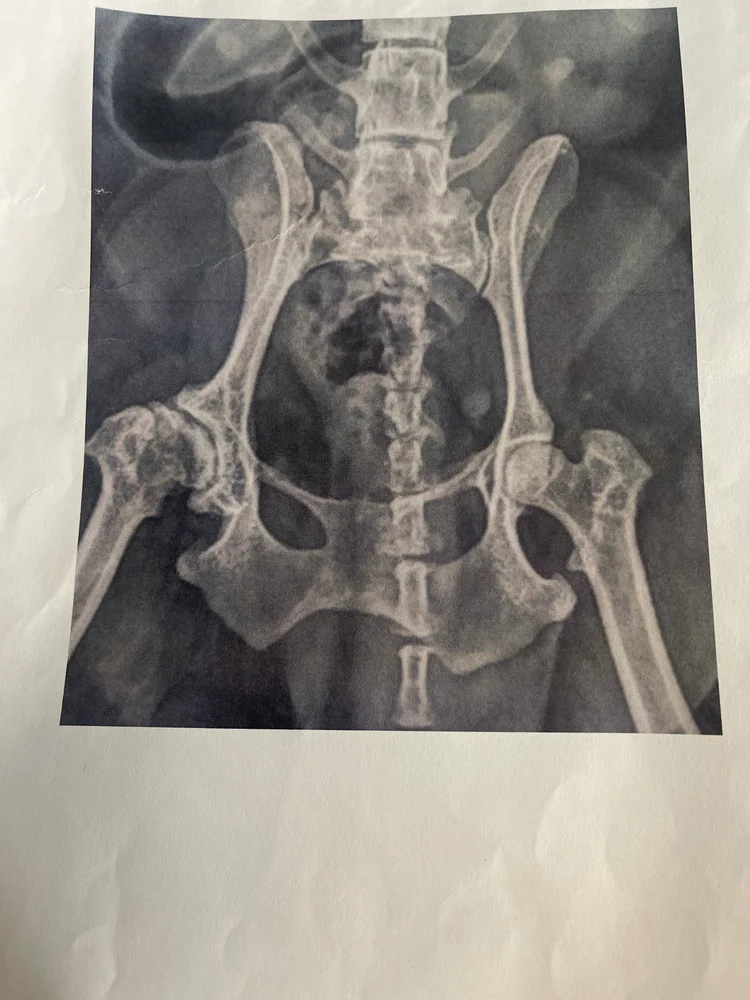

Vårt kjæreste familiemedlem fikk plutselig sterke smerter i magen🥺. Buken ble så stram at jeg måtte ta henne til dyresykehus. Der viste det seg at av ukjente grunner hadde det samlet seg opp så mye gass i magen som ikke ville gå videre at hun måtte tømmes for gass. Men fordi vi måtte ha både ultralyd og røntgen fant de også flere ting med vår lille skatt. Hun hadde forkalkning i rygg og høyre hoftekul.

Det ble også oppdaget en syste på eggstokken. Og det er årsaken til denne spleisen. Akkurat nå er livmoren frisk men Vetrinær anbefalte oss på det sterkeste å fjerne livmoren til Pixi. Hun opplever svært mye smerte i løpetid på grunn av den, og risiko for andre komplikasjoner minskes dramatisk hvis den fjernes mens livmoren er frisk. Dette dekkes ikke av forsikring som vi har den beste av. Vi har alltid vært forsvarlig med våre dyrevenner men nå strekker vi ikke til. Min kjære mann som Pixi reddet livskvaliteten til når hun kom inn i vårt liv er uføre og jeg er barne og ungdomsarbeider. Bare egenandel på denne runden gjør at vi ikke går rundt. Legger ved bevis fra siste undersøkels med funnene og håper det finnes gode sjeler der ute som kan avse noen kroner❤️